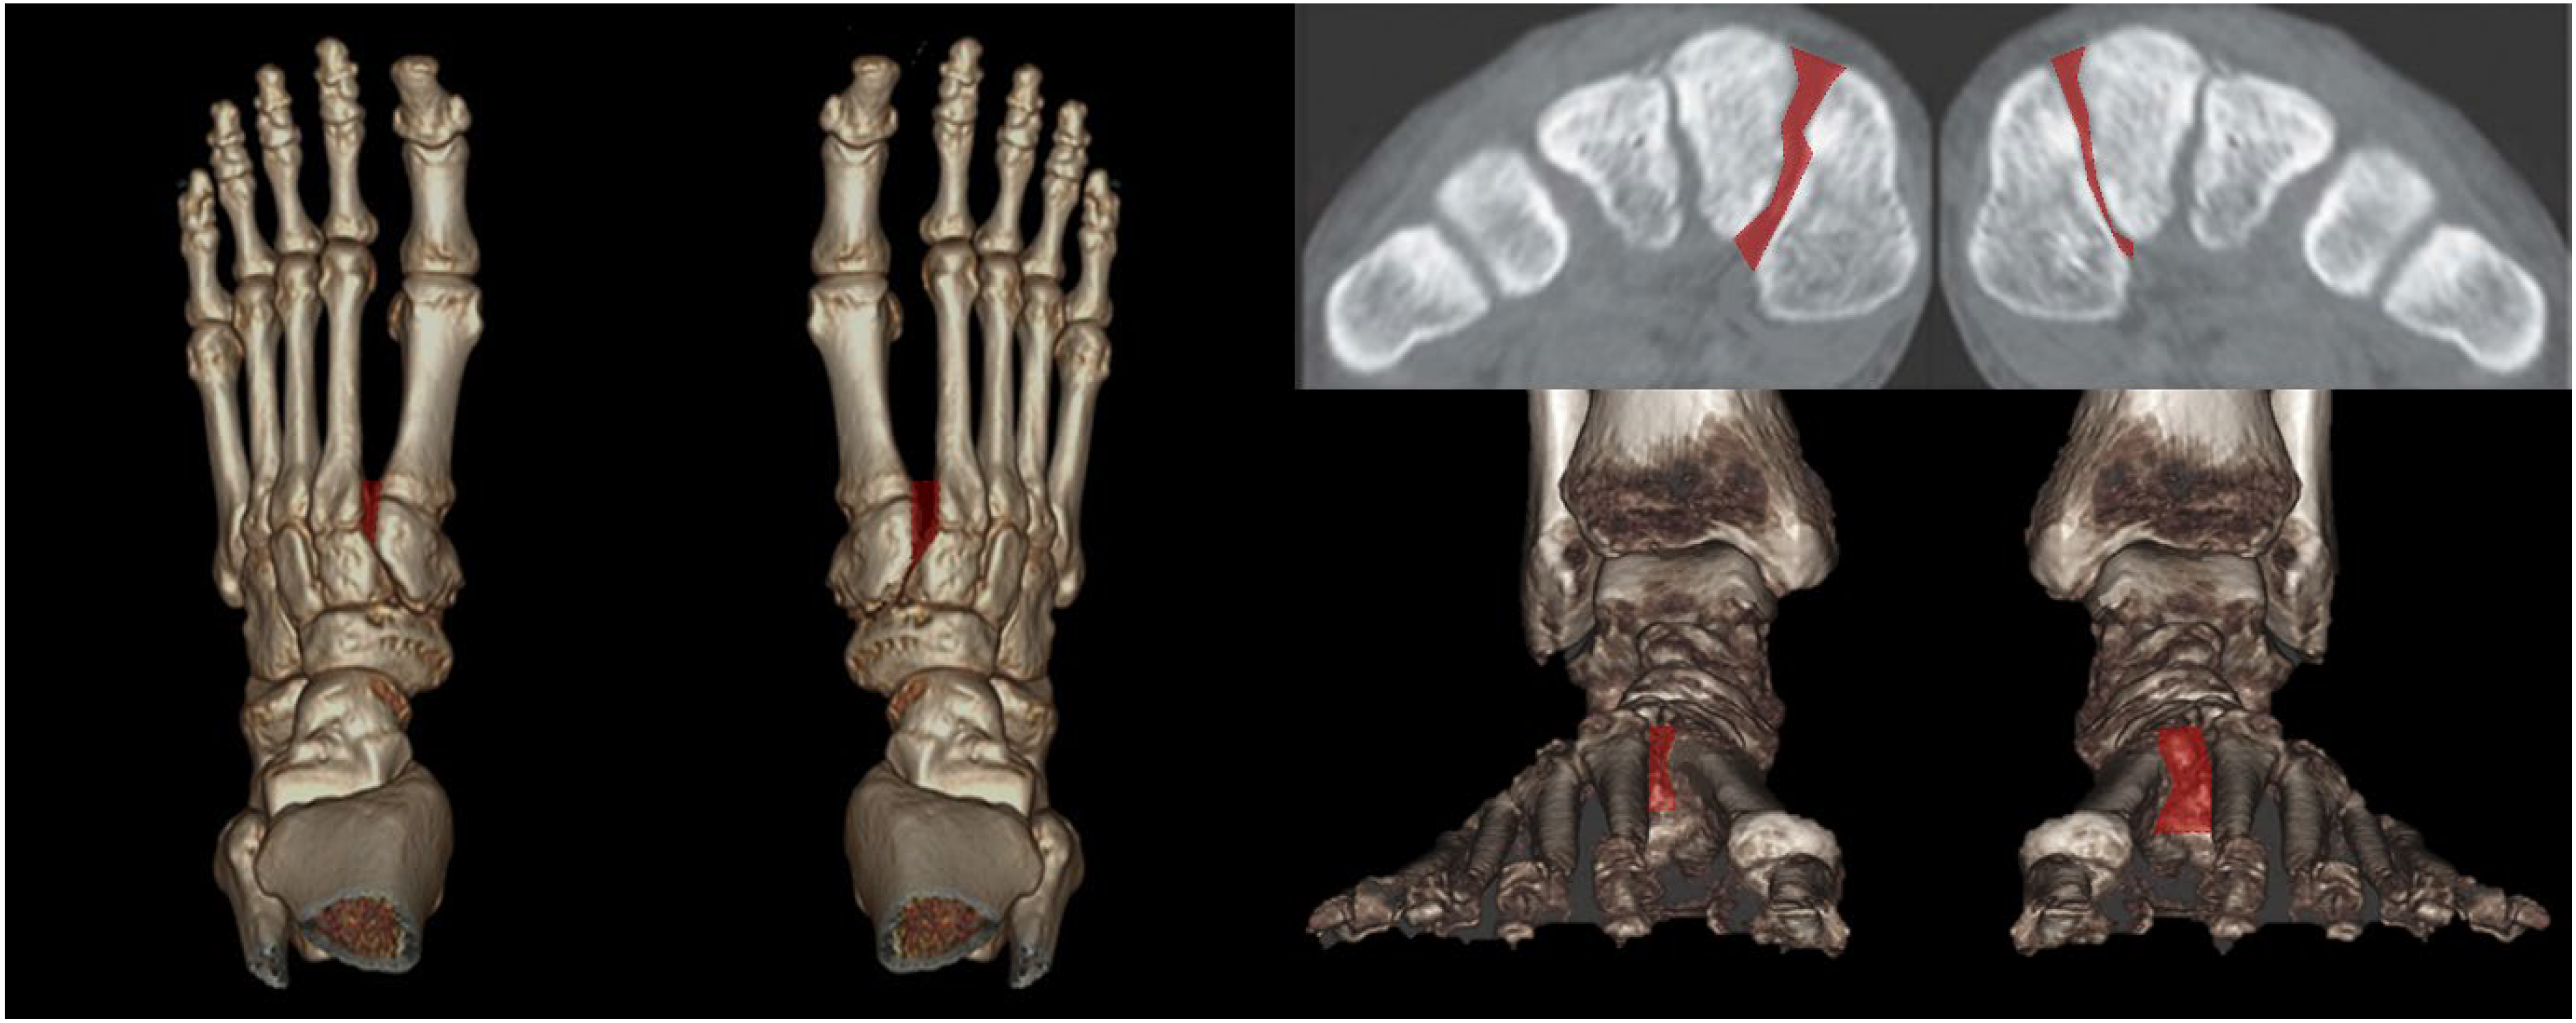

Instead of conventional axial measurement of the Lisfranc joint, some novel WBCT parameters have been developed and introduced for use in the clinical setting. Sripanich evaluated 96 cadaveric specimens and designed a WBCT protocol to enhance the reliability of Lisfranc joint measurements [29]. They found that measuring the distance between the medial cuneiform and second metatarsal with coronal WBCT imaging would be a reproducible way to localize the interosseous Lisfranc ligament injury. Similarly, Bhimani et al. evaluated the Lisfranc joint complex using one-dimensional (1D), two-dimensional (2D), and 3D measurements on WBCT scans among operatively confirmed Lisfranc instability (Figure 5) [30]. They concluded that coronal 3D volumetric measurement had higher sensitivity and specificity than 2D and 1D measurements because the second metatarsal tends to displace both laterally and superiorly in Lisfranc injury. Despite its inherent limitation in being actively used in acute conditions, WBCT may enhance diagnostic accuracy for suspicious Lisfranc injuries with uncertain conventional radiograph findings.

Figure 5.

3D volumetric measurement of the Lisfranc joint.